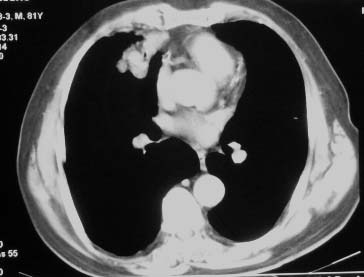

右肺中叶病灶境界基本清晰,肺窗上似见血管伸入,增强后明显强化,考虑动静脉瘘可能吧!

右中动静脉瘤